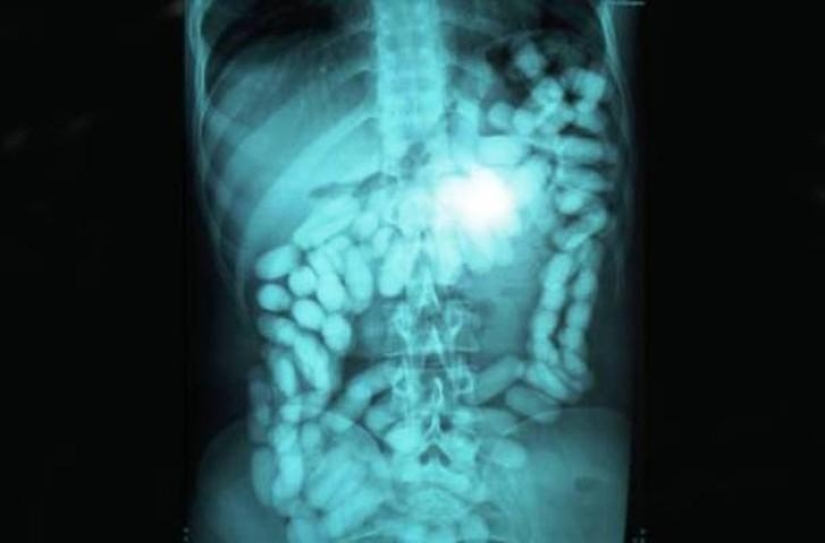

23. Metanfetaminas.